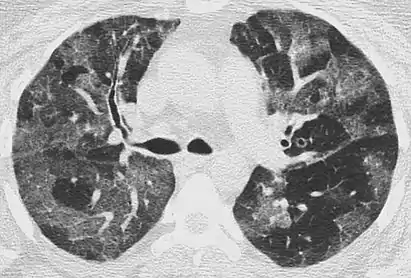

High-resolution CT image showing ground-glass opacities in the periphery of both lungs in a patient with COVID-19 (red arrows). The adjacent normal lung tissue with lower attenuation appears as darker areas.

Ground-glass opacity is among the most common imaging findings in patients with confirmed COVID-19.[16][17] One systematic review found that among patients with COVID-19 and abnormal lung findings on CT, greater than 80% had GGOs, with greater than 50% having mixed GGOs and consolidation.[16] GGOs with mixed consolidation has most often been found in elderly populations.[18] Several studies have described a pattern among initial, intermediate, and hospital discharge imaging findings in the disease course of COVID-19. Most commonly, initial CT imaging reveals bilateral GGOs at the periphery of the lungs. During initial stages, this is most often found in the lower lobes, although involvement of the upper lobes and right middle lobe has also been reported early in the disease course.[16][18] This is in contrast to the two similar coronaviruses, SARS and MERS, which more commonly involve only one lung on initial imaging.[19][20] As the COVID-19 infection progresses, GGOs typically become more diffuse and often progress to consolidation.[11][18] This is sometimes accompanied by the development of a crazy paving pattern and interlobular septal thickening.[18] In many cases the most severe pulmonary CT abnormalities occurred within 2 weeks after symptoms began.[17] At this point, many individuals begin showing resolution of consolidation and GGOs as symptoms improve. However, some patients have worsening symptoms and imaging findings, with further increase in septal thickening, GGOs, and consolidation. These patients may develop lung "white-out" with progression to acute respiratory distress syndrome (ARDS) requiring treatment escalation.[17][21]